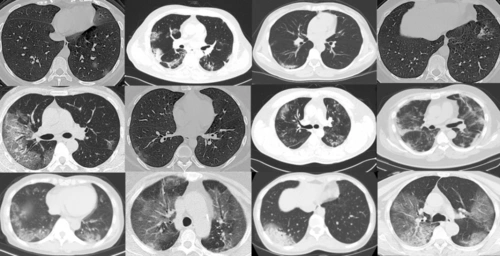

新冠肺炎呈阳性的 ct 扫描图像示例. 方法

支原体肺炎跟病毒肺炎一样,可以家庭内传播,这篇ct入门教你鉴别

【影像读片】病毒性肺炎ct

什么肺炎的ct影像如此与众不同